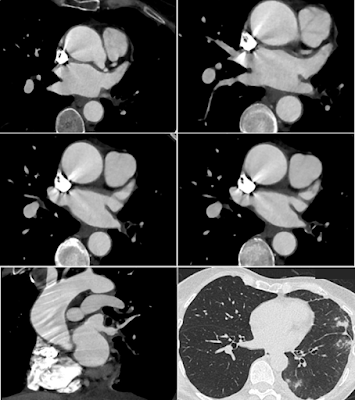

A 60-year-old woman presented with intermittent left-sided chest pain and hemoptysis that had persisted for several weeks. Her medical history included paroxysmal atrial fibrillation, for which she underwent catheter ablation four months prior. A chest radiograph revealed minimal left-sided pleural effusion with stable parenchymal scarring but no focal consolidation.

Subsequent CT angiography (CTA) revealed severe focal stenosis in the superior segment of the left inferior pulmonary vein, and possible occlusion or high-grade stenosis in the basal segment. Multifocal ground-glass opacities (GGO) and peripheral consolidation were noted in the left lower lobe and lingula, raising suspicion for pulmonary venous congestion.

CT Angiography (CTA) is the modality of choice for diagnosis. Key findings include:

• Focal narrowing or occlusion of pulmonary veins

• Delayed contrast opacification of the affected vein

• Ground-glass opacities and septal thickening in the corresponding lung segment

• Pleural effusion, particularly ipsilateral to the stenosed vein